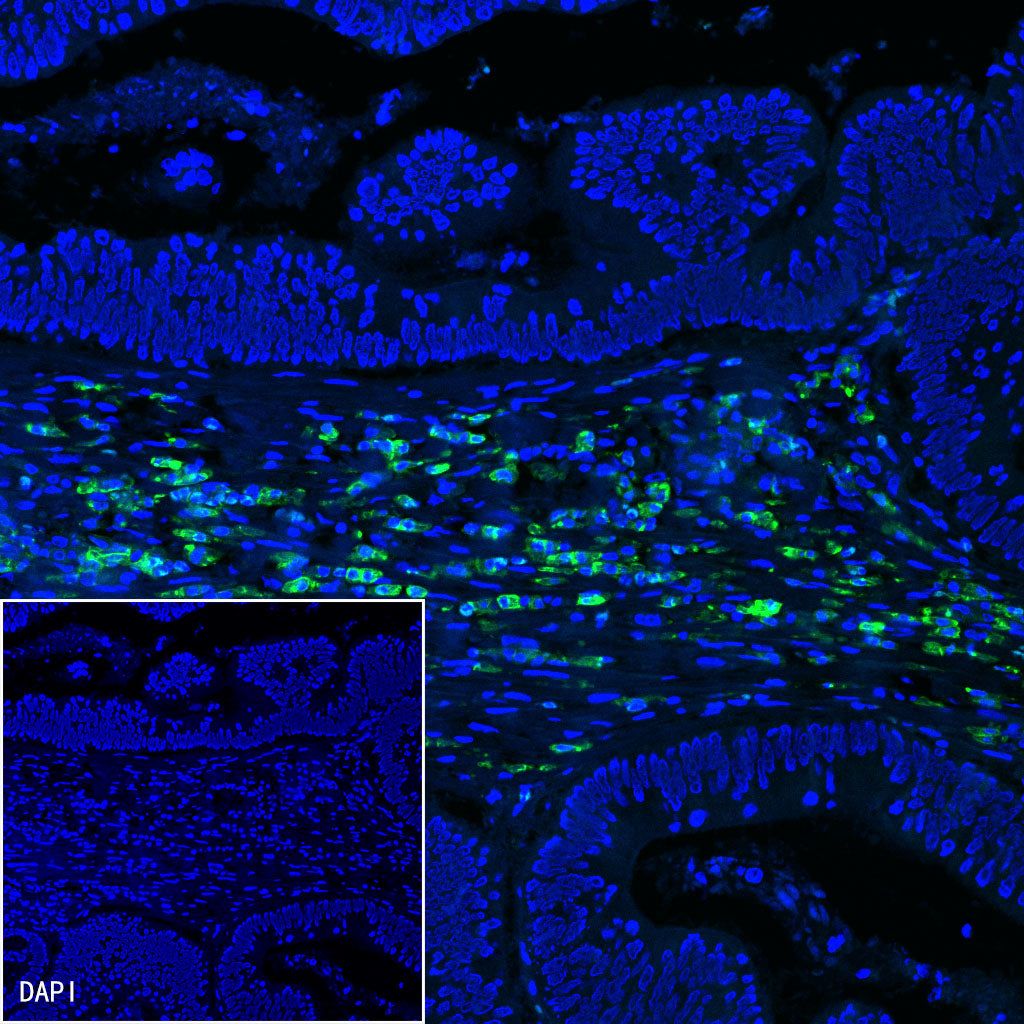

Immunofluorescence

IF shows positive staining in paraffin-embedded human colon cancer. Anti-CD38 antibody was used at 1/500 dilution (Green) and incubated overnight at 4°C. Goat polyclonal Antibody to Mouse IgG - H&L (Alexa Fluor® 488) (S0B4017) was used as secondary antibody at 1/500 dilution. Counterstained with DAPI (Blue). Heat mediated antigen retrieval with EDTA buffer pH9.0 was performed before commencing with IF staining protocol.